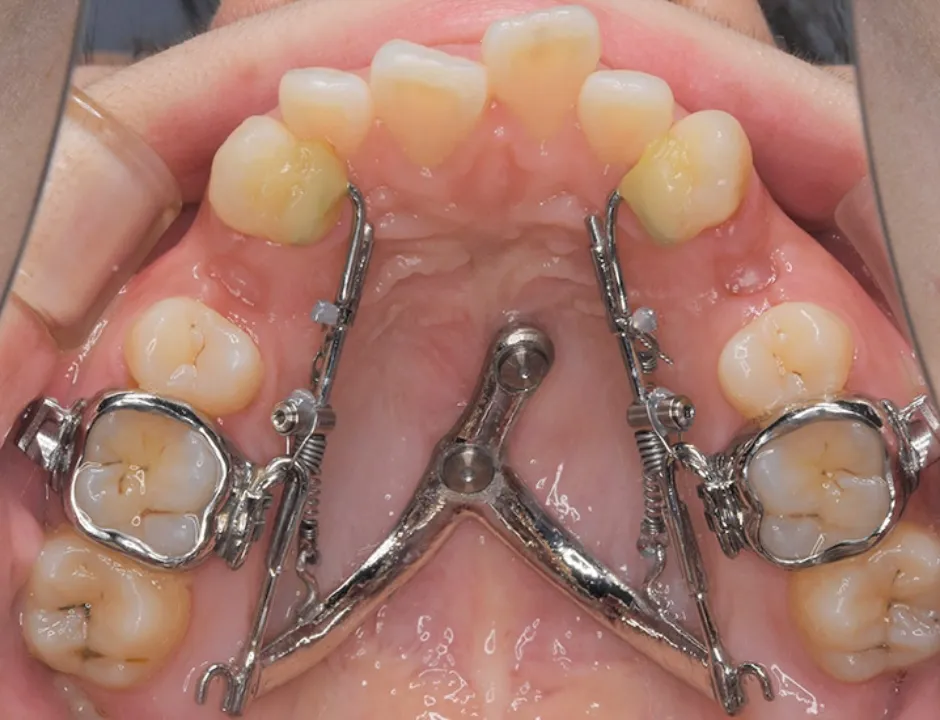

具体的には、3Dスキャナーを使用して、アンカースクリューのヘッド部、上顎の天井の粘膜、歯の3次元的な位置関係をデータとして取得し、そのデータを基にCAD/CAM技術を駆使して矯正装置を設計・製作します。この3Dメタルプリント矯正装置は、歯への適合性と強度に優れており、幅広い症例に対応が可能です。

デジタル技術の進歩により、現在では3Dスキャナーで取得した患者様の口内の3Dデータを基に、CAD/CAM技術を活用して矯正装置の設計から作製まで行なうことが可能です。矯正用アンカースクリューと連結できる矯正装置も、3Dメタルプリント技術を用いて、患者様一人ひとりに合わせて精密に設計・製作することにより、対応可能な症例の幅が広がっています。

SHU-lider® EX(拡大)

上顎急速拡大と大臼歯遠心移動が同時に可能